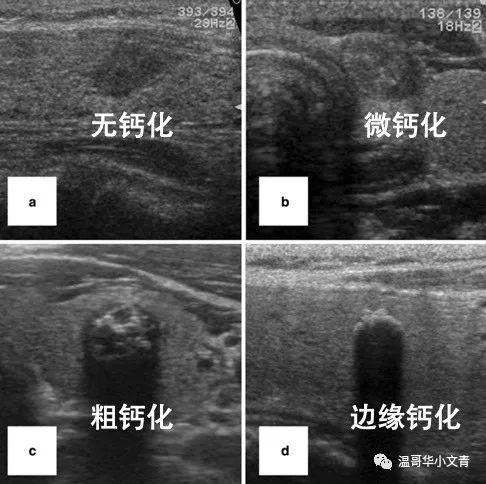

甲状腺癌的钙化程度不同

肿瘤发展的可能性会有所不同

图a是无钙化,b是微钙化

它们今后发展的可能性相对大一点

图c是粗钙化,d是边缘钙化

它们今后发展的可能性相对小一些